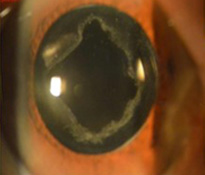

백내장 증상 7가지 7. 눈 색상 변화

심한 정도가 덜한 경우에는 노란색의 음영이 나타나기도 하고, 가장 정도가 심할 때는 갈색으로 나타납니다. 갈색으로 눈 색이 변색되었을 때는 이미 백내장이 많이 진행되었다는 신호라고 볼 수 있습니다.